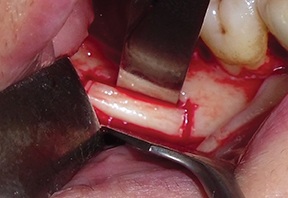

To make osteotomy execution easier, it is advisable to mark them directly on the cortical bone with a pencil (Fig. 6).

Using an ultrasonic device with dedicated T-Black inserts (ES007T and ES009NT), a cortico-cancellous bone block was outlined and osteotomized (Figs. 7–8).

Fig. 6: Osteotomies marked on the cortical bone with a pencil

Block by Block

Fig. 7: Osteotomy performed with an ultrasonic tip (ES009NT)

Fig. 8: Osteotomy performed with an ultrasonic tip (ES007T)